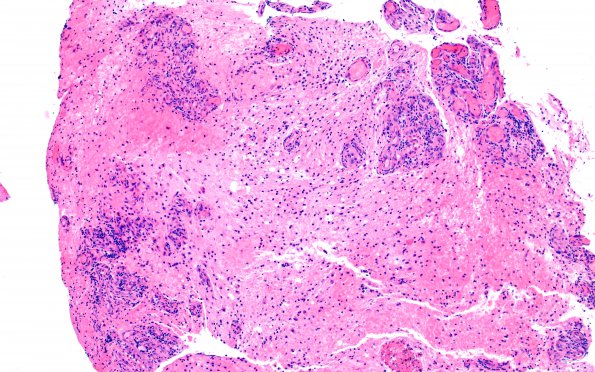

Washington University Experience | MYELIN (NON-IMMUNE MEDIATED) | Retinal Vasculopathy with Cerebral Leukoencephalopathy (RVCL, TREX1 Mutation) | 15B2 CRV (Case 15) A3 H&E 10X 2

Higher magnification of a portion of the specimen shown in image #15B1 (H&E)